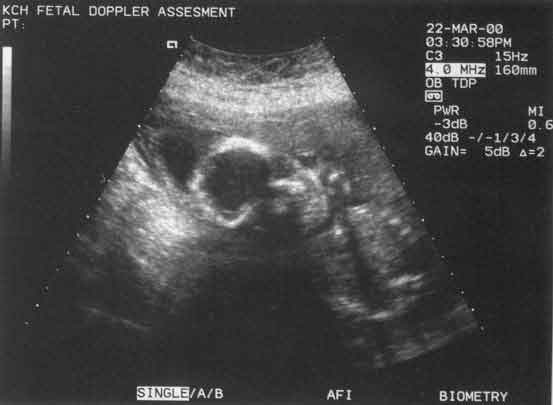

scan

pregnant